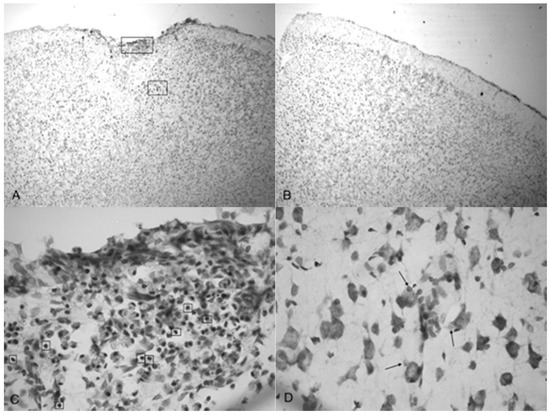

3.4. Histological Assay

Microphotographs of cresyl violet stained tissue from 3.4 bar TBI treatment (Figure 4A,C) show indentation and fragmentation of the cortex exactly where the acoustic wave was administered to two separate rats. The opposing panels (Figure 4B,D) show intact, unaffected tissue in the contralateral cortex at the same stereologic orientation (approximately +3.0 anterior to bregma). In addition, the cells in Figure 4A,C appeared to be more sparsely distributed in the damaged region, suggesting neurodegeneration and disruption of neural pathways. Similar histological profiles were observed with 4.2 bar sections.

Figure 5A shows the TBI-targeted left frontal cortex 10 days after 5.0 bar acoustic wave treatment. Note the severely damaged cortex compared to 3.4 bar treatment cortex (see Figure 4A,C). While the histology from the 3.4 bar treatment revealed moderate impairment of the dura mater and the arachnoid layer, the 5.0 bar treatments showed significantly more damage to post-TBI tissue that ranges well beyond the pia mater. The intact contralateral cortex showed no damage (Figure 5B). Also, no additional damage was detected in any other brain region of the TBI-treated rats, including the hippocampus.

Figure 5C,D are higher magnification photomicrographs taken from the highlighted regions of Figure 5A (Figure 5C upper region, Figure 5D lower region of Figure 5A). Figure 5C shows the damage taken from the damaged impact zone at the top of the infarct. Very few intact pyramidal neurons remain in this region. Notice the lightly stained granulated cells that appear to be leukocytes infiltrating from capillaries due to disruption of the blood-brain barrier [29]. Figure 5D shows the continuation and persistence of damaged cells throughout the parenchyma of the infarct region with the arrows showing granulated cells. These cells are most likely macrophages that have phagocytized blood products or other injured cells [29]. Large reparative astrocytes and condensed dark cells can be seen in Figure 5D as well.

Figure 4. Microphotographs show the tissue from the frontal cortex visualized with cresyl violet from 60 day-old Han-Wistar rats, 10 days post-injury. Images indicate the damage from the acoustic wave 3.4 bar TBI targeted left frontal cortex as shown in the left panels (A,C) and compared with the contralateral, unaffected right frontal cortex (B,D) from the matching animals. Panels (A,C) show indentation and fragmentation of the cortex where TBI was administered while panels (B,D) show intact, unaffected tissue. In addition, the cells in A and C are more sparsely detected, suggesting neurodegeneration and disruption of neural pathways in these animals. All photomicrographs were taken at 40× magnification.

Figure 5. Photomicrographs taken of the frontal cortex stained with cresyl violet from two Han-Wistar rats, 10 days post-TBI from 5.0 bar acoustic wave. Image (A) shows the TBI-targeted left frontal cortex and Image (B) shows the contralateral intact right cortex at the same stereologic section. Indentation and damage of the cortex can be easily seen in the TBI-damaged hemisphere (40× magnification). Images (C,D) are higher magnification photos (100×) taken from the boxed regions ((C) from the upper box, and (D) from the lower box) of image (A). These images show the presence of condensed dark cells, neuroprotective astrocytes, and granulated cells, which are likely macrophages that have phagocytized blood products. The boxes in image (C) highlight the condensed dark cells, and the arrows in image (D) highlight granulated cells, likely macrophages that have phagocytized blood products.

Indentation and fragmentation of the surface of the frontal cortex was observed where the acoustic waves were administered and focused (Figure 4 and Figure 5). The severity of the acoustic TBI has been shown to correlate with the acoustic wave intensity (Figure 6 and Figure 7). Figure 5C shows injured compacted neural cells, many of which appear condensed and dark. Figure 5D shows the perimeter of the infarct area visualized by the condensed dark cells. The impact from the 5.0 bar treatment severely ruptured blood vessels in the dura mater and the subarachnoid space before penetrating down past the pia mater, evidenced by granular phagocytized blood cells or the remnants of neurons (dark cells), also seen in Figure 5C. These images (Figure 5C) show the presence of phagocytic leukocytes near the impact zone, illustrating that the force from the TBI fractured blood vessels and caused the blood–brain barrier to rupture at least temporarily. Mukherjee et al. [29] suggested that these observed macrophages have entered into the TBI infarct to phagocytize the newly entered blood cells which elicits a yellowish stain from ingested red blood cells (these cells do stain yellow in the original color photomicrographs). The upregulation of expressed cytokines may also attract the infiltration of neutrophils to aid in cellular repair but may also lead to further degradation of the blood–brain barrier [5].

The pervasive nature of the acoustic wave is best observed beyond the initial point of impact. Figure 5A,B as well as Figure 5C,D show the difference in the neuronal cells on the impacted side (A, C, and D) and non-impacted side (B) 10 days after TBI. The cells from the damaged, left cortex are enlarged, and appear to be more disorganized and skewed than comparable cells in the right hemisphere. There are many hypertrophic astrocytes that have moved in to help repair the vascular brain injury, a sign of the increased severity of the injury [32].